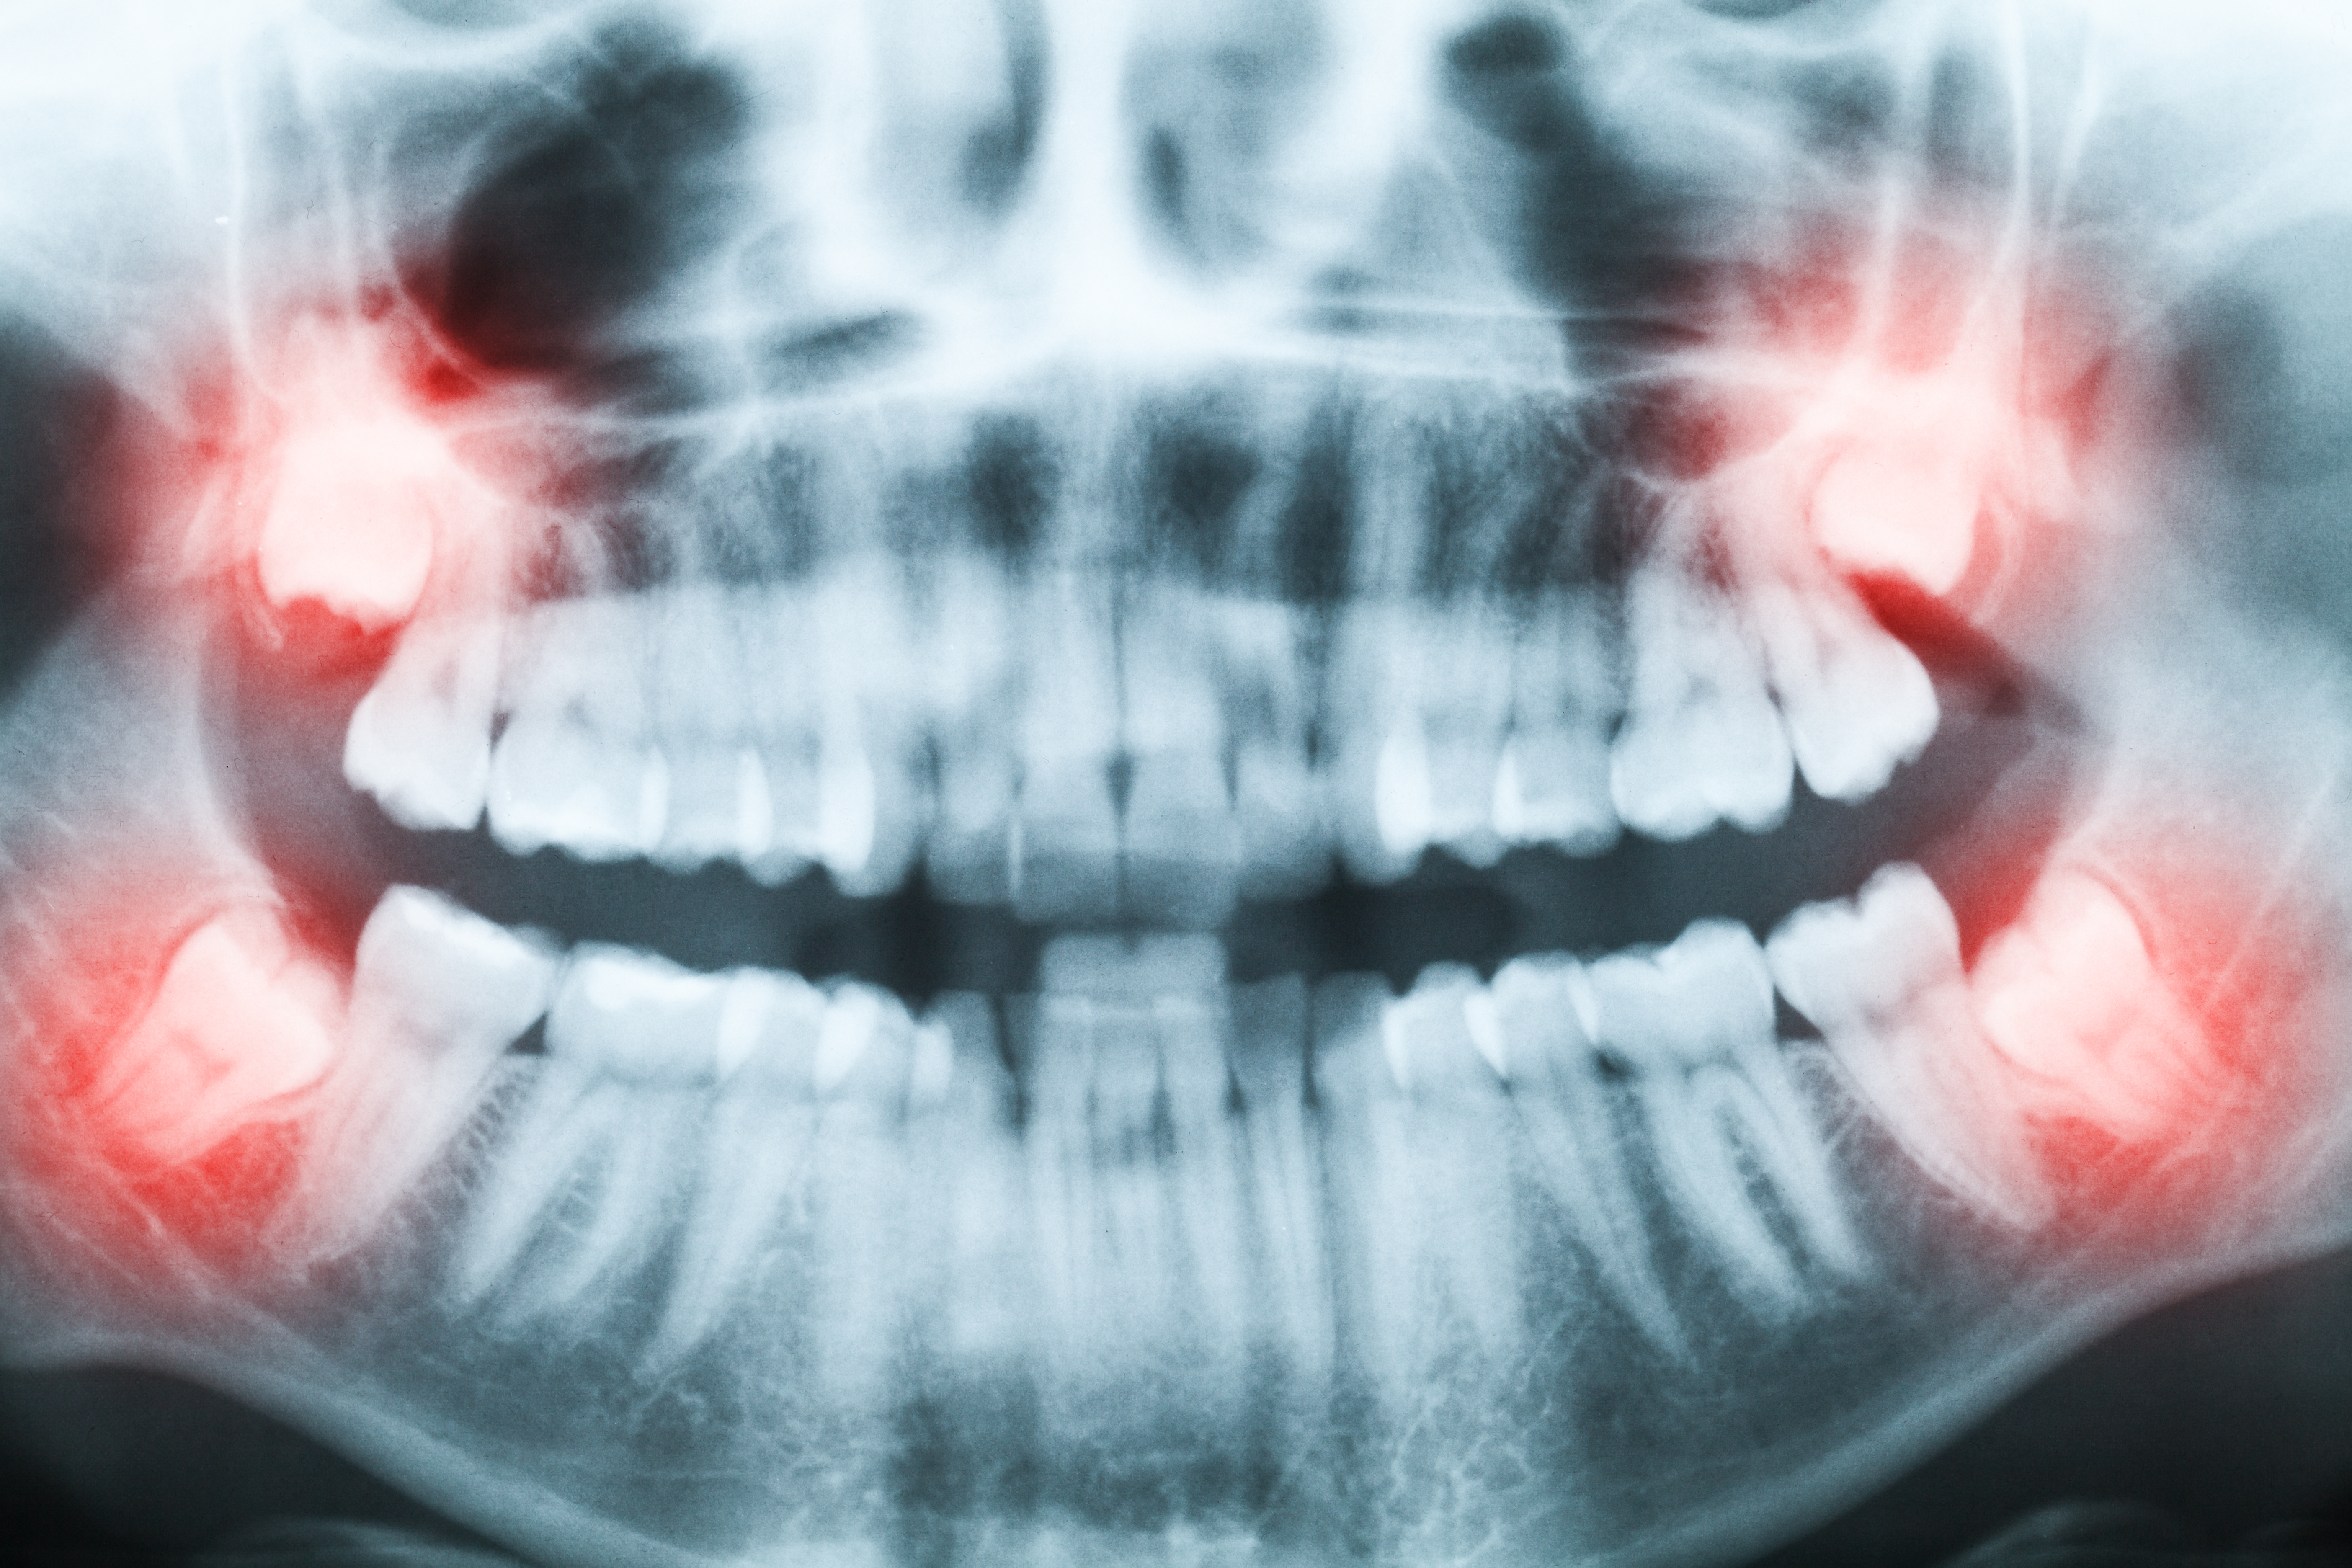

Byron Leiva, cirujano oral y maxilofacial, dice que las cordales tienen variedad de formas y tamaños dependiendo de cada paciente. Su anatomía puede tener entre una y cuatro raíces, así como entre uno y seis conductos.

“La edad de erupción es entre los 18 y 25 años, aunque pueden aparecer en una edad más temprana, más avanzada, o no aparecer siquiera. En algunas ocasiones no erupcionan las cuatro muelas, sino solo algunas de ellas”, explica.

Sin embargo, dice el cirujano Leiva, muchas veces las muelas de juicio no tienen espacio para crecer como corresponde y pueden causar problemas, e incluso crecer en diversos ángulos de la mandíbula, a veces, incluso de forma horizontal.